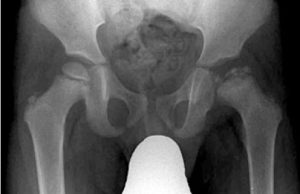

Entre los ejemplos clásicos de osteocondrosis encontraríamos la Enfermedad de Legg-Calvé-Perthes (cabeza femoral, ver imagen), Enfermedad de Köhler (escafoides tarsal), Enfermedad de Freiberg (cabeza del segundo metatarsiano) y Enfermedad de Scheuermann (cuerpos vertebrales).

- Enfermedad de Legg-Calvé-Perthes. Cabeza femoral. 4-8 años.